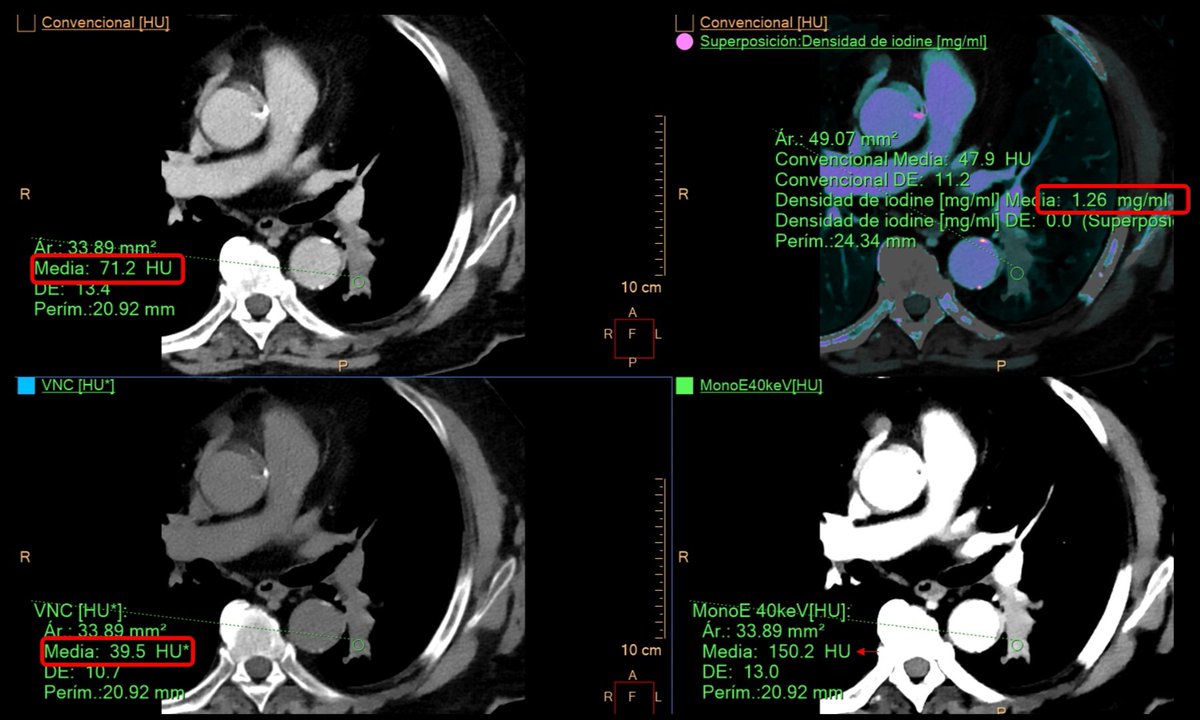

Attention to #spectral images! Gopal Punjabi ⚠️ The endobronchial content is enhancing --> solid! 1️⃣Virtual non-contrast (VNC)= 39HU 2️⃣Conventional= 71UH (>20UH compared to VNC) 3️⃣ Iodine density =1.26 mg/ml